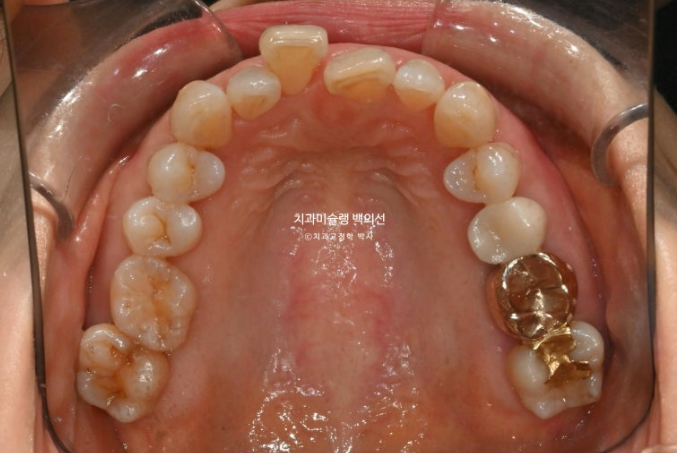

파란 화살표 치아는 잇몸이 검붉게 보입니다.

엑스레이상 이미 치주염이 상당히 진행이 되어 발치가 불가피한 상황이였습니다.

위 앞니는 잇몸이 꽉 잡아주지를 못해서 점점 솟아 내려오고 튀어나오면서 치아사이가 벌어졌습니다.

작은어금니도 안으로 쓰러져 있어서 이 부분은 윗니와 엇갈려 물리는 가위교합 입니다.

아래 앞니를 하나 빼어 그 공간으로 치아를 가지런히 하고 솟아내려온 위 앞니를 원위치 시키는 교정을 하기로 했습니다.

치주적으로 이미 상당히 약해진 상태에서는 거창한 치료계획을 세우지 않습니다.

문제가 되는 부분을 집중적으로 움직이며 다른 치아에는 불필요한 치아이동을 최소화 하여 잇몸부담을 줄입니다.

인비절라인 라이트로 앞니 배열, 솟아내려온 치아의 함입, 과개교합 해결, 가위교합 해결등을 목표로 치료에 들어갔습니다.